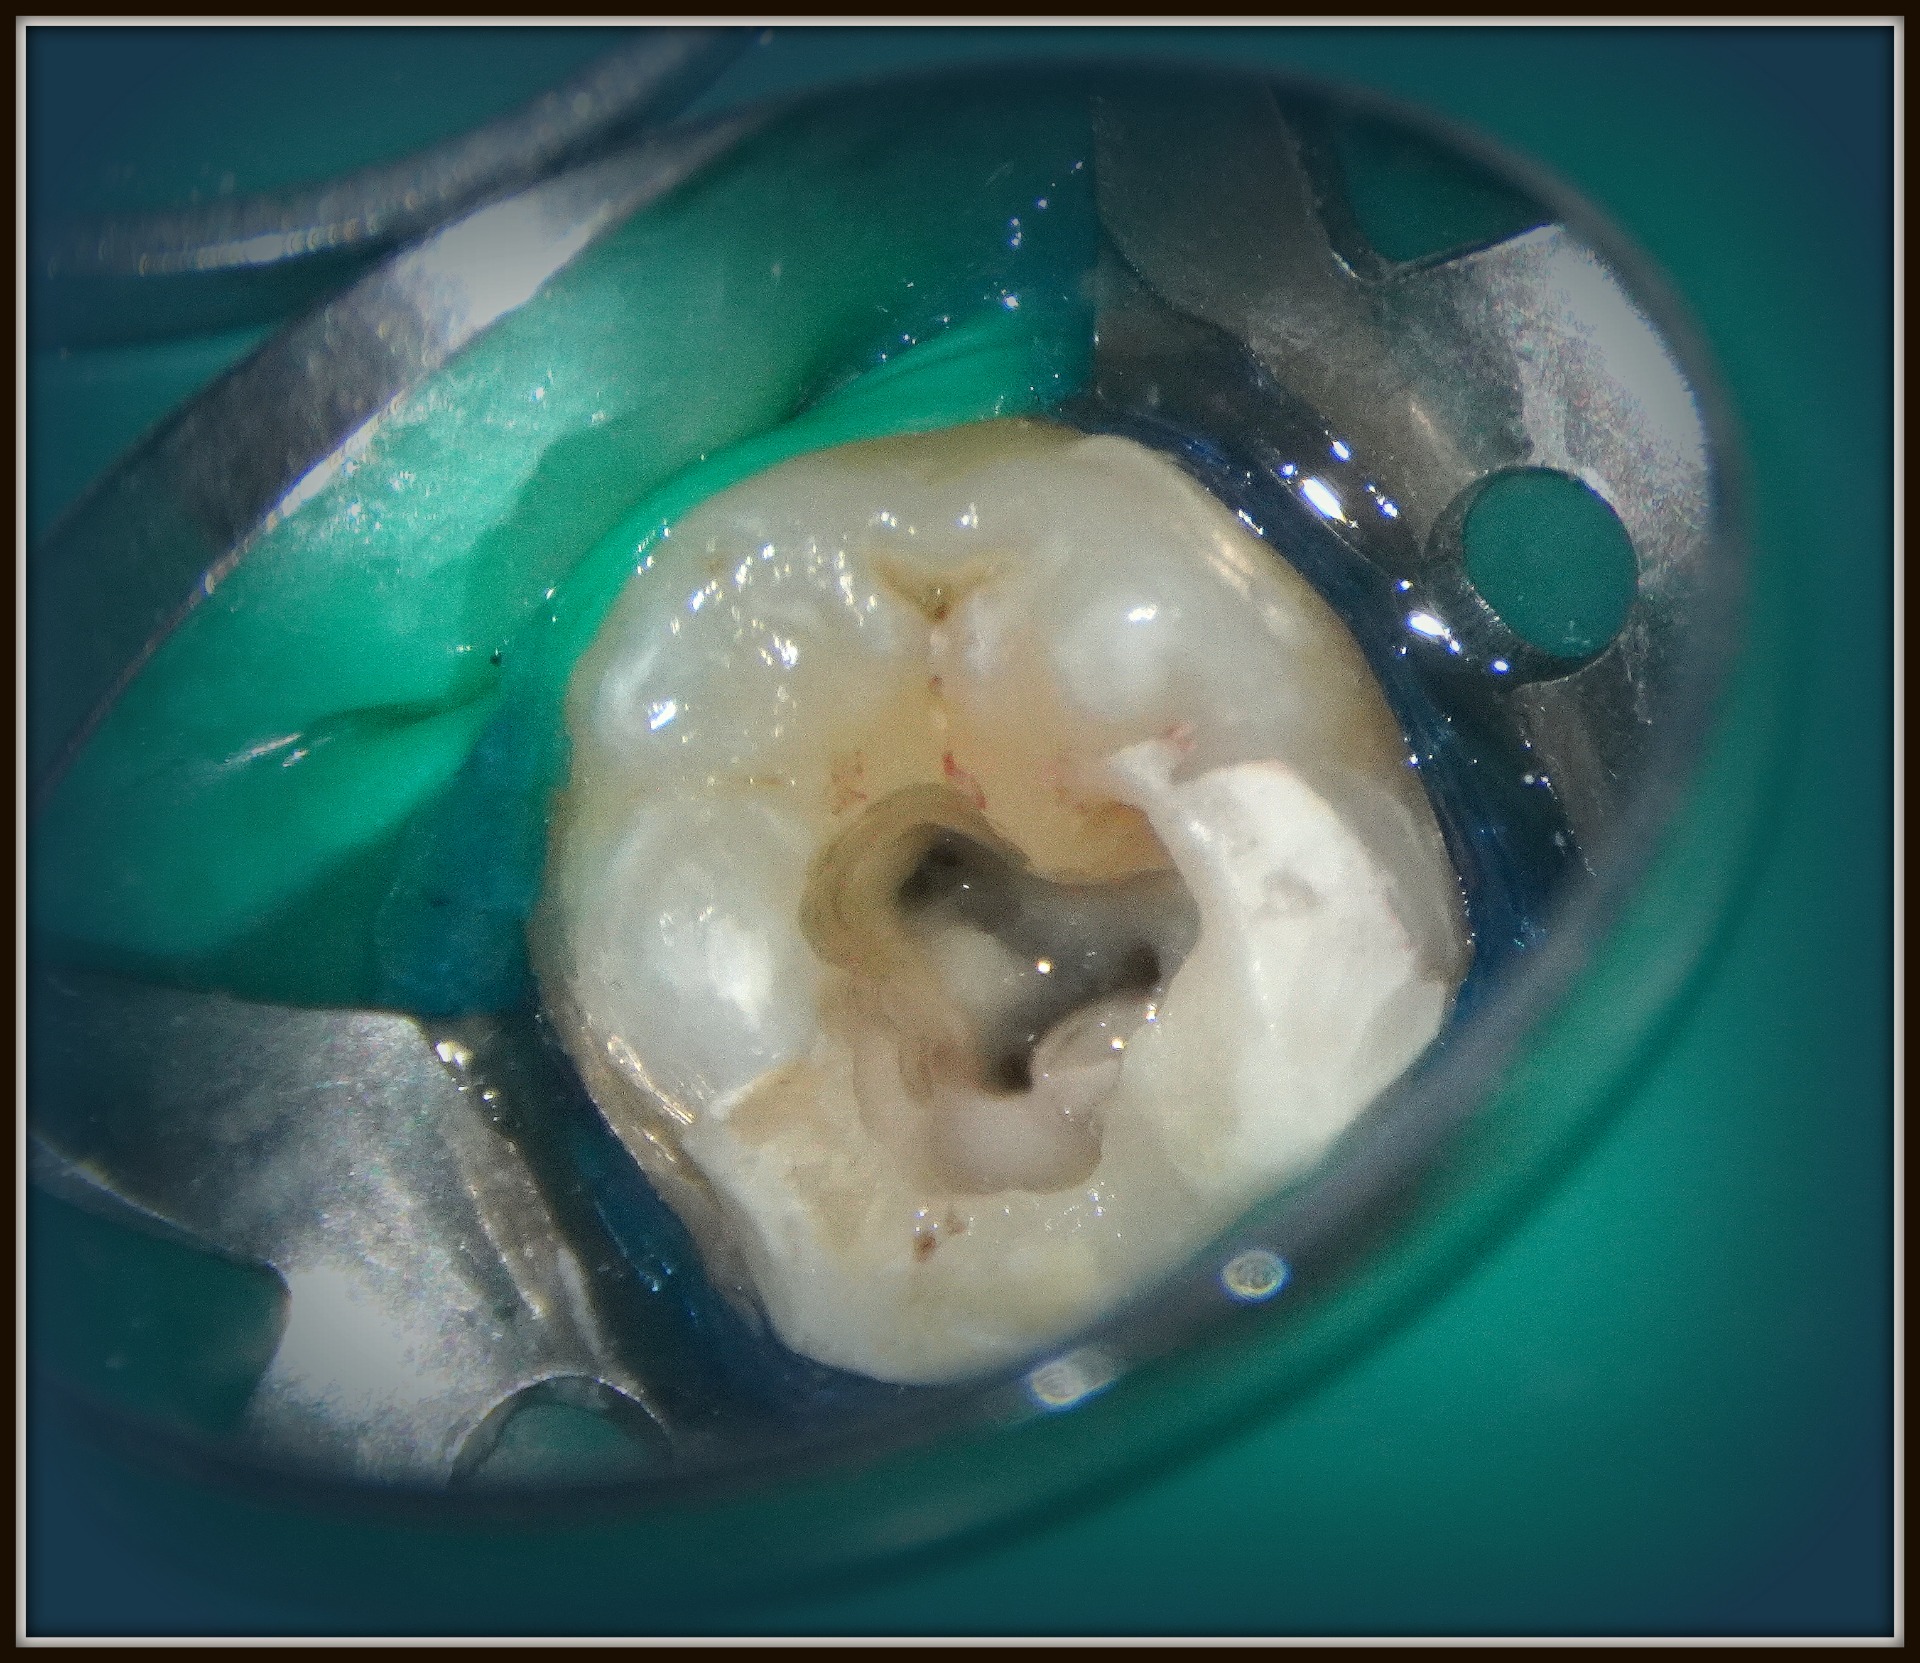

Mikroszkópos gyökérkezelés

Mikroszkópon keresztül sokkal jobb rálátással, sokkal kontrolláltabban, precízebben lehet fogbél-kezeléseket végezni. Így a kezelés sikeressége is biztosabb.